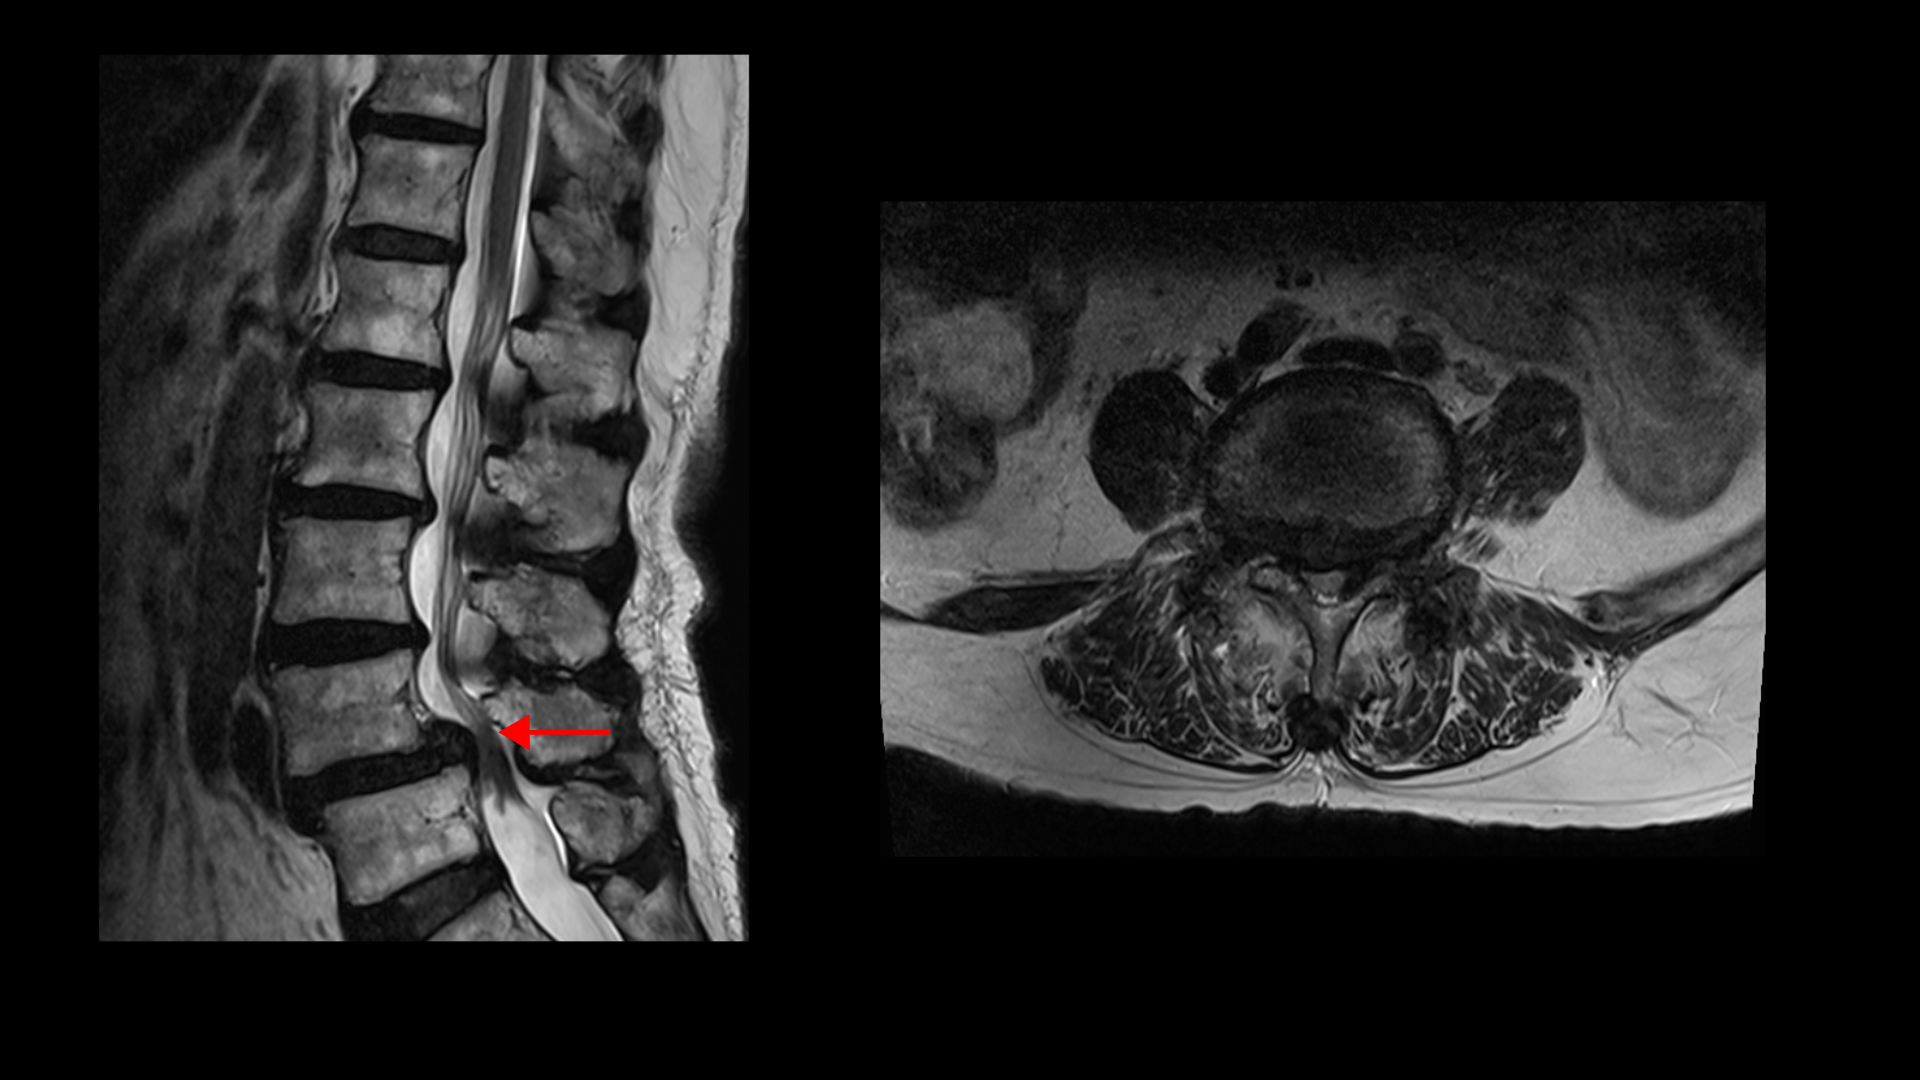

이 환자분 상태를 먼저 설명 드린 후 이분 말씀을 들어보겠습니다. 이분은 협착증을 앓으신 지 약 7년 정도 되셨습니다. MRI를 보면 여러 마디에 퇴행성 디스크가 있고

4번, 5번에는 전방전위증이 있습니다.

전방전위증이 있는 4번, 5번 마디에서는 오른쪽, 왼쪽 신경가지가 나가는 양쪽 추간공이 모두 좁아져 있고

그리고 척추관도 황색인대가 심하게 두꺼워지면서 중심성 협착도 매우 심합니다.

이 환자분의 근육을 MRI에서 보면 5번, 1번 마디에서 기립근과 장요근을 체크해봤을 때 기립근의 지방화 정도도 심하고 장요근, 특히 왼쪽 장요근은 거의 형체를 알아보기 어려울 정도로 위축이 심한 상태입니다.